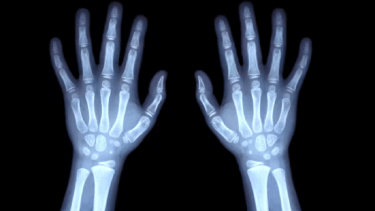

Sí. Entre los procedimientos usados para determinar la madurez de un individuo destacan, principalmente, las radiografías, que permiten estimar de manera segura la edad biológica de los niños y adolescentes analizando el aspecto de los distintos núcleos de osificación de los huesos de la mano.

Los métodos numéricos parten de una radiografía de la muñeca y el carpo izquierdo y les asignan una puntuación en función del grado de madurez observado en distintos puntos de osificación, que se desarrollan de manera secuencial a medida que sumamos años.

Si comparamos tres radiografías de la mano de un niño, una persona joven y un adulto, a simple vista comprobaremos que los huesos del carpo en la infancia están lejos de alcanzar el tamaño y la forma definitivas que tendrán en la edad adulta.

Los métodos cualitativos se basan en la comparación, bien de una radiografía del carpo o bien de una panorámica de mandíbula (ortopantomografía), con una imagen de referencia disponible en un atlas radiológico ordenado siguiendo una secuencia cronológica de las distintas etapas de la maduración ósea.